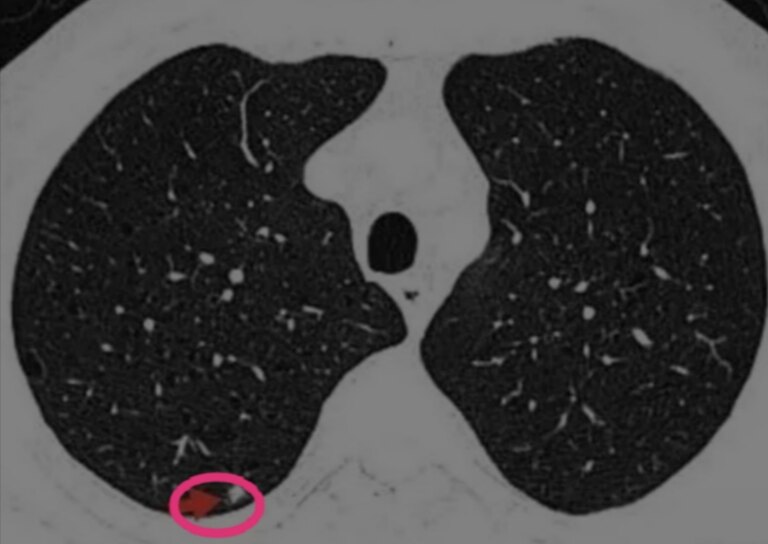

马上再来看一下这个患者肺结节4个月之前的胸部CT图像:

可以看到,这个肺部实性结节四个月之内有增大趋势。这个时候就更需要警惕了。那么,是否可以就此确定这个肺部微小实性结节就是肺癌吗?还是不行,因为右上肺尖后段为结核好发部位,结核也可能短期内增大。

这里有个需要注意的点:4个月短期增大的肺部实性结节,要么是恶性程度很高的肺癌,低分化神经内分泌癌(或者转移性),要么是炎症性(包括结核)。

回看患者5年前(2015年)的胸部CT,该相同位置,表现为一个肺部微小的磨玻璃结节。

这显然不符合肺结核以及其他肺部炎症结节的生长规律,病史上可以排除肺结核和肺部炎症。

至比,我们认为这个肺结节是恶性的可能大,患者接受微创胸腔镜手术切除,术后病理为神经内分泌癌。